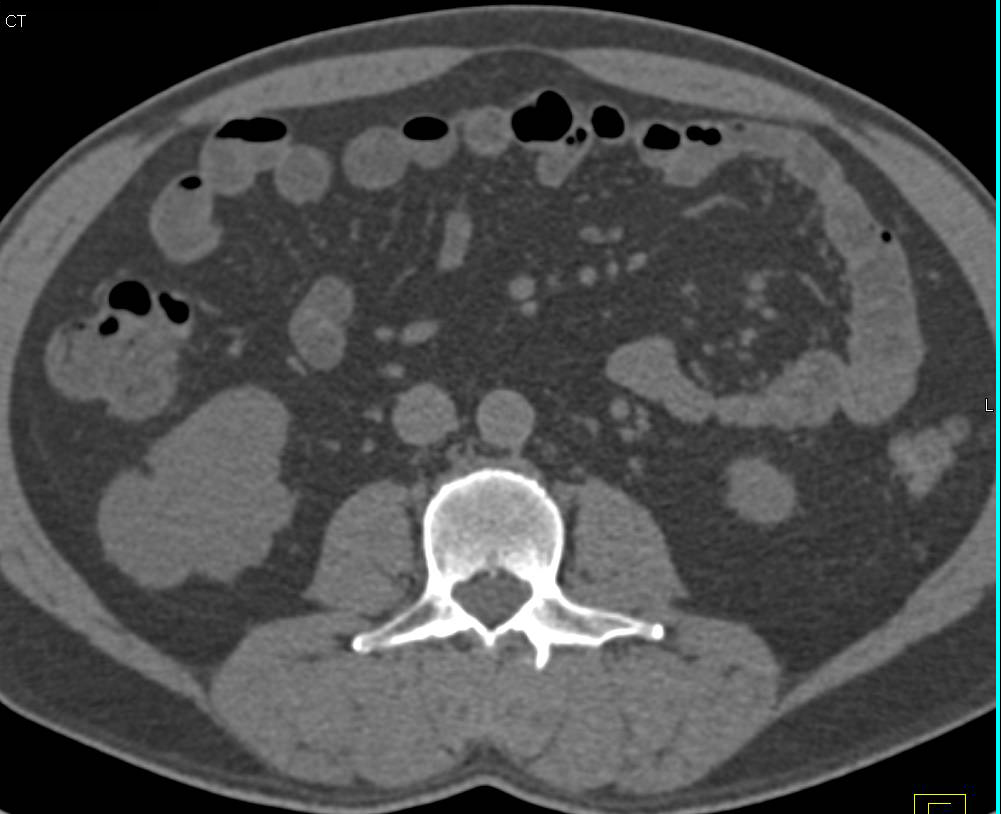

Renal Artery Stenosis